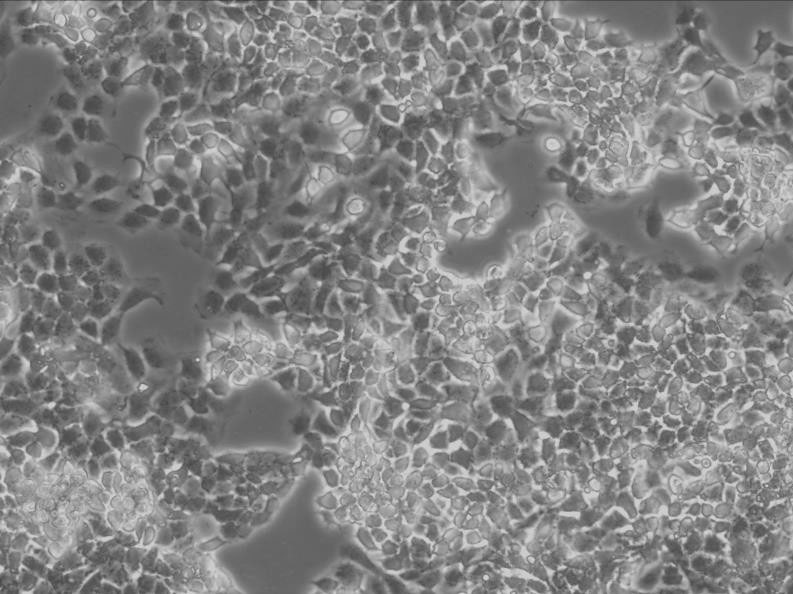

NCI-H748细胞:人小细胞肺癌细胞系

细胞形态:上皮细胞样

细胞生长:贴壁

细胞生长特性:悬浮生长